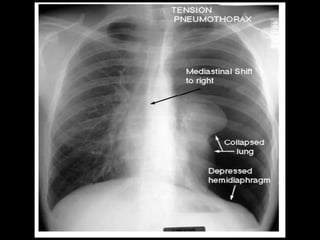

Chest X-ray :-

• Hyper translucency between the lung & thoracic cage.

• Razor sharp border of the collapsed lung.

• Shifting of mediastinum on the opposite side of injury.

Tension pneumothorax :- 1.The communication between the lung and pleural cavity is small and is valvular. 2. It allows air entry during inspiration but prevents it from escaping during expiration. 3. Therefore, pleural pressure is more than the atmospheric pressure.

Tension pneumothorax :- •Displacement of the mediastinum with respiration. • Dyspnoea. • Cyanosis. • Tachycardia. • Increased respiratory rate. • Decreased blood pressure. • Respiratory failure.